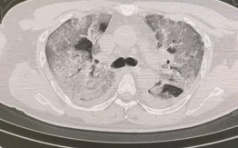

在这个甲型流感肆虐的冬季,一位32岁的体型健壮男性患者因“发热伴咳嗽咳痰1天”被120紧急送入瑞金医院嘉定院区急诊。急诊检查显示甲流阳性,指脉氧仅54%,病情迅速恶化并出现昏迷,PCO2高达12.0 kpa,CT显示肺部呈现“白肺”。在温珍亮医师的陪护下,患者经气管插管后入住重症医学科。